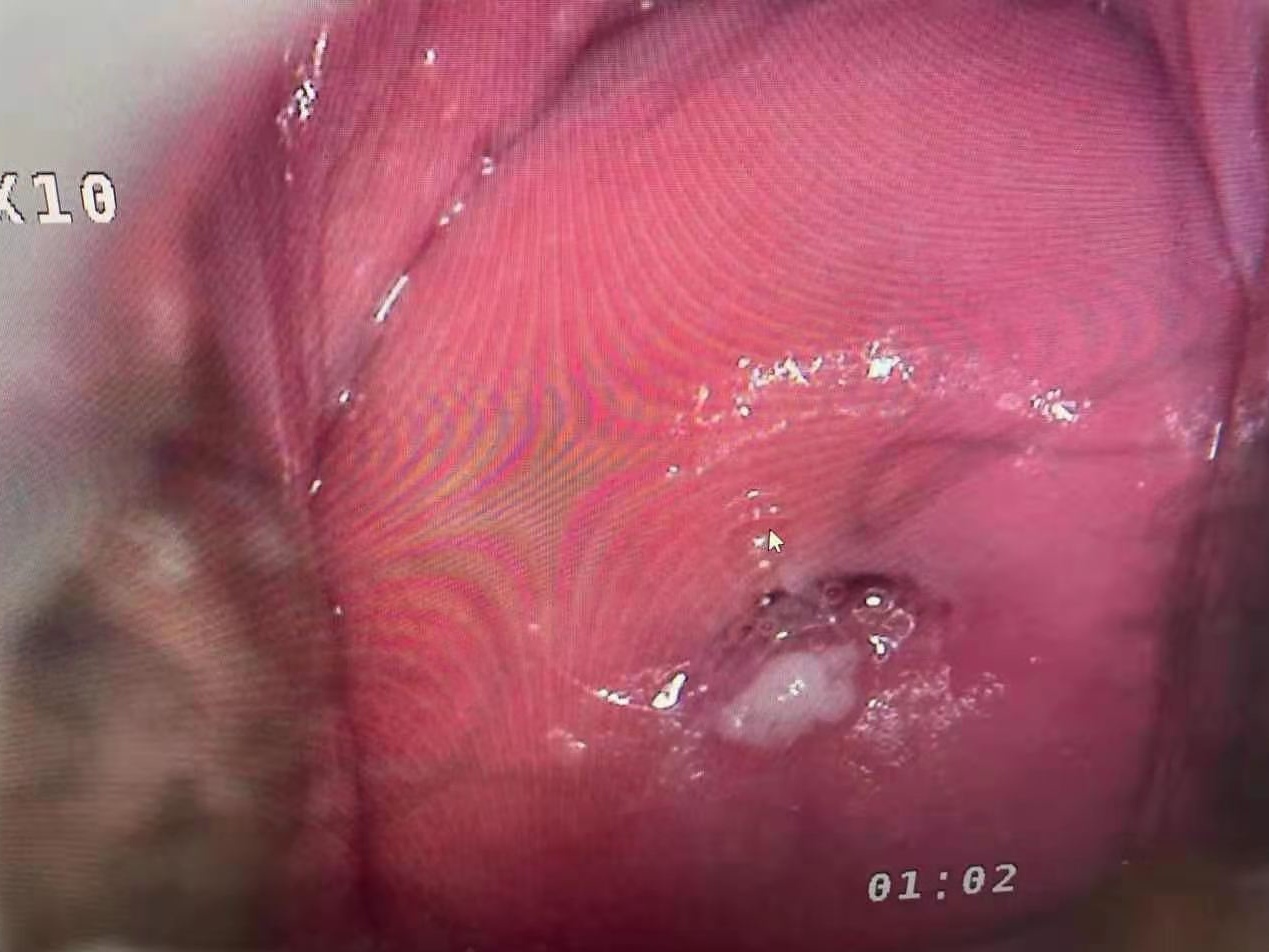

Real cervical diagnosis pictures